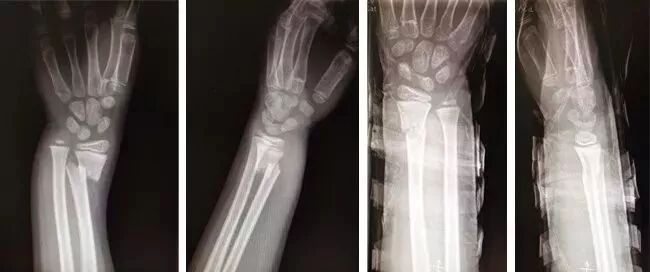

病例二

鎖骨骨折術(shù)后再骨折

患者李某,女,60歲,鎖骨骨折內(nèi)固定術(shù)后一年,鋼板螺釘取出后又骨折,分離約2cm,當(dāng)?shù)囟嗉裔t(yī)院就診后均建議再次進行手術(shù)治療,患者由于經(jīng)歷過一次手術(shù),再也不愿意接受第二次。

后經(jīng)人介紹來到嘉興邦爾骨科醫(yī)院富陽骨傷就診,予以“8”字繃帶固定,內(nèi)服中藥,每周換幫,半年之后骨折終于愈合。

手法整復(fù)前后對比圖